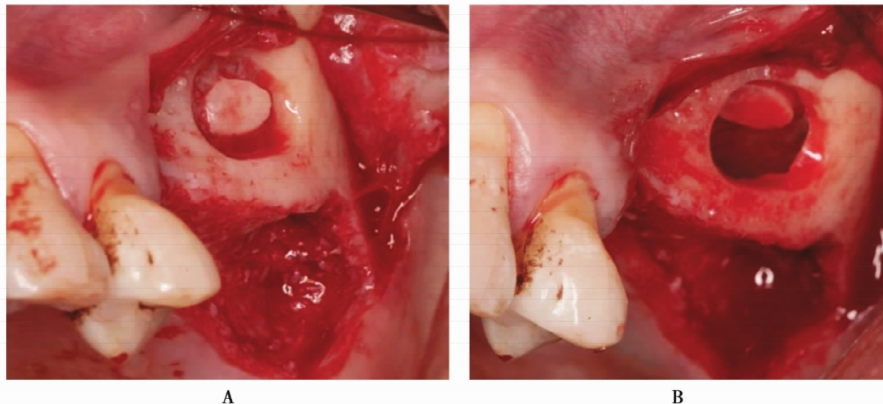

图2 侧壁开窗及分离上颌窦黏膜A.形成开窗口;B.分离窦黏膜

超声骨刀侧壁开窗,剥离上颌窦黏膜(图13A)。但在剥离的过程中,由于开窗中央骨块锐利的边缘,侧壁上颌窦黏膜发生穿孔(图13B)。采用胶原膜封闭穿孔后,植入Bioss®骨粉,采用延期种植。

图13 侧壁开窗A.超声骨刀开窗;B.分离窦黏膜,但出现小的穿孔